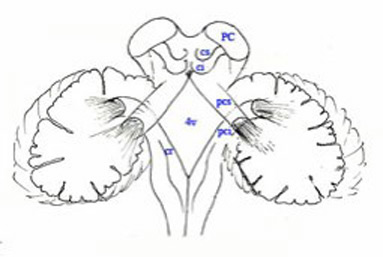

Le schma sous-jacent sera utilis, en

repres utiles au trac des diffrentes voies.

Sch.20 – Canevas du nvraxe |

Dchiffrer les lgendes partir du

haut : - Les chiffres : numrotation des aires corticales fronto-parito- temporales.. - T : Thalamus - PC : Pdoncule Crbral - nr : noyau rouge - s, m, i : pdoncules crbelleux

sup., moyen & infer. - v4 : Losange dlimitant le 4”

ventricule - np : noyaux pontiques - nf : noyau fastigial |

- ni : noyaux interposs - nd : noyau dentel - nv : noyaux vestibulaires - nvl : noyau vestibulaire latral - :ZL : Zone latrale - Zi : Zone intermdiaire - Zm ; Zone mdiale - Zfn : Zone floculo-nodulaire - ob : olive bulbaire - nC : noyau de Clarke - fscd : faisceau spino-crbelleux

dorsal - fscv : faisceau spino-crbelleux

ventral |